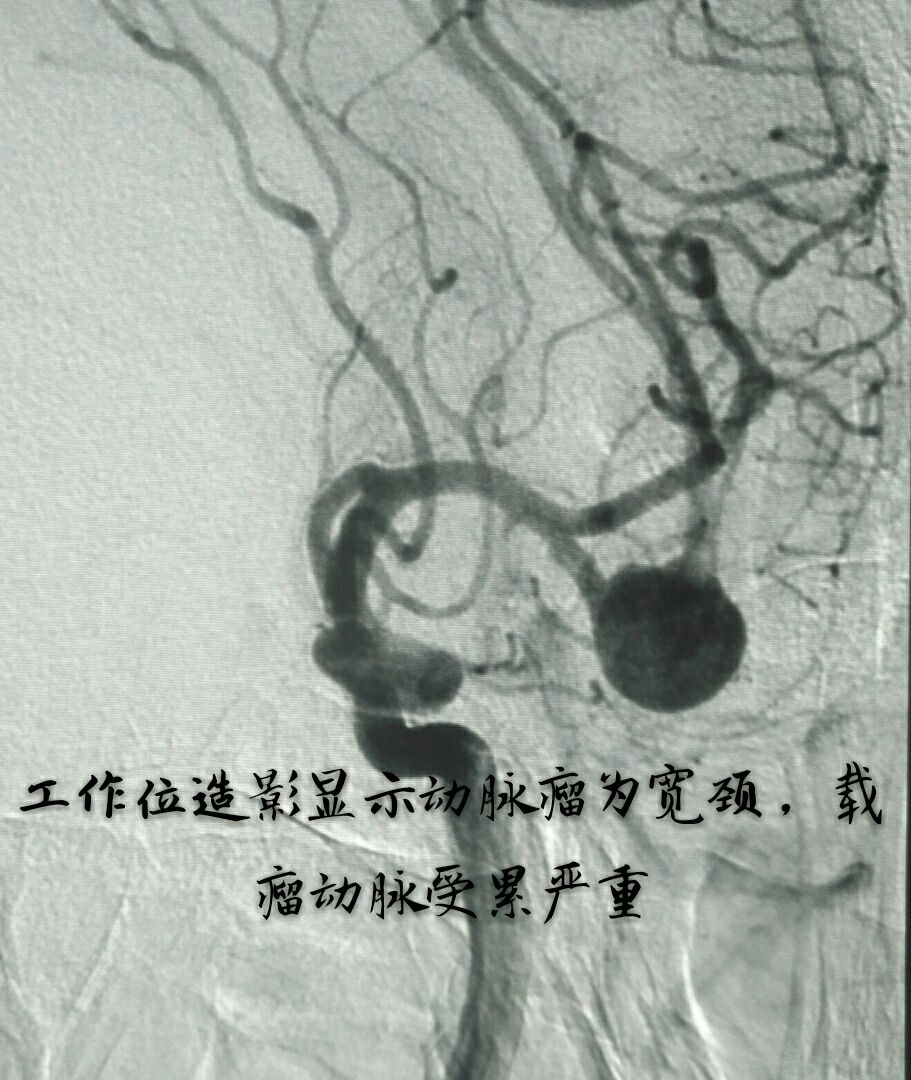

病例四:80岁男性患者,主症:头痛、脑鸣2年,DSA示左侧大脑中动脉下干大动脉瘤,绝对宽颈,载瘤动脉累及程度重

因栓塞难度大,术前做了详细、精准的计划

最准致密栓塞动脉瘤,载瘤动脉完美塑型并受到保护,难点:瘤颈极宽,辅助支架导管通过动脉瘤到达远端困难,最准微导管塑型成大弯,微导丝成袢通过动脉瘤到达远端,成功释放支架,动脉瘤栓塞后患者头痛、脑鸣症状消失